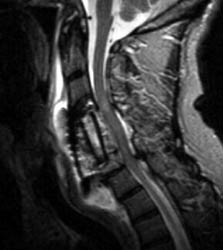

Sagittal T2 FSE (A), sagittal T1 pre (B) and post contrast

administration (C) show the graft with blooming artifact where the

plate exists anteriorly as well as the screw (lower portion of the image). The

susceptibility artifact of the screw shows its ventral positioning essentially

outside of the C7 vertebral body. Also, there is T2 hyperintense fluid

surrounding the surgical site with the graft material is now surrounded by

nonenhancing mixed signal intensity material, predominately hypointense on T1

and hyperintense on T2, possibly suggesting some blood products. There is

enhancement in both the anterior and posterior epidural spaces. The distal end

of the fixation plate with the screw in the C6 vertebral body appears now

displaced anteriorly and there is significant prevertebral soft tissue swelling.

Also, this fluid- like material surrounding the bone graft appears to cause some

narrowing of the spinal canal, with some mild spinal canal stenosis.